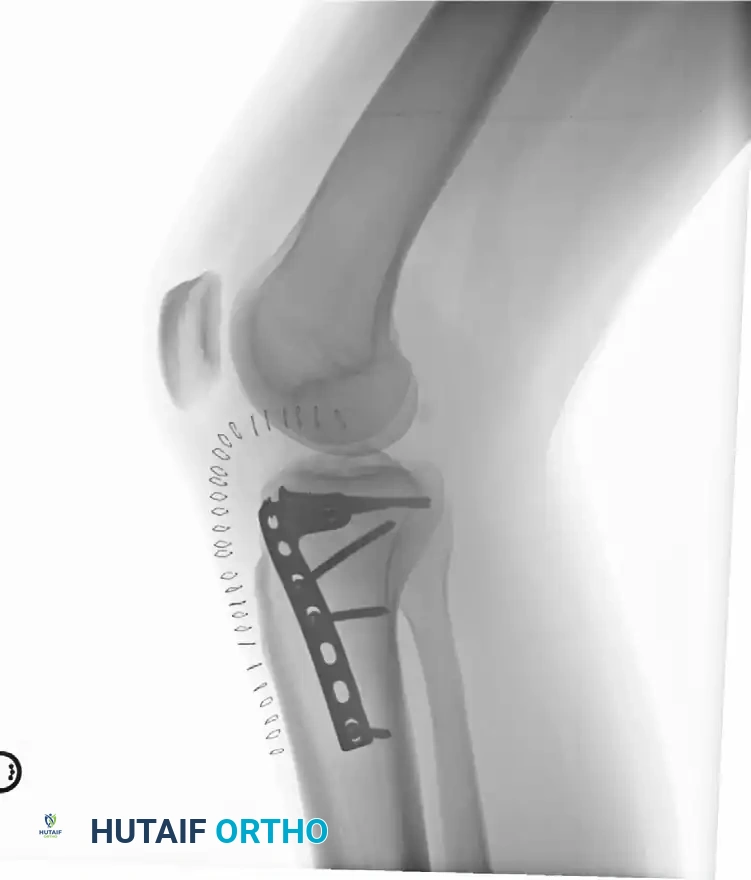

5. Fixation: The lateral cortex is supported with a pre-contoured lateral periarticular locking plate acting as a buttress.

3. Fixation: This approach allows direct access to the posteromedial apex of the fracture. An anti-glide or buttress plate is applied to resist the sheer forces of the medial femoral condyle.

* Hybrid Fixation: The modern gold standard for these severe injuries is a hybrid approach. A method of lateral plateau plating combined with temporary medial external fixation (as described by Mast) is highly effective. Alternatively, limited open reduction of the articular surface with percutaneous screw fixation, followed by the application of an Ilizarov fine-wire circular frame, provides excellent biomechanical stability while completely respecting the biology of the traumatized soft tissues.